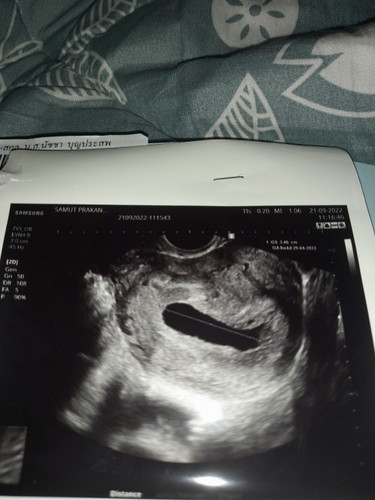

ซาวด์รอบแรกตอน8w เจอแต่ถุงการตั้งครรภ์ 2.3 cm วันนี้ไปซาวด์รอบ2 10w พบแต่ถุงการตั้งครรภ์เหมือนกันแต่ถุงมีขนาดใหญ่ขึ้นตอนนี้3.4 cm คุณหมอบอกให้ยุติการตั้งครรภ์แต่แม่กลับมารอให้น้องหลุดเอง มีโอกาศไหมคะที่จะซาวด์เจอน้อง#ขอบคุณล่วงหน้านะคะ #ขอคำแนะนำหน่อยค่ะ #ท้องแรกคะ